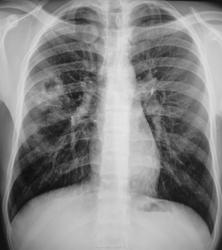

А, фамилия юноши, вдруг, показалась мне знакомой. Мы, недавно его «однофамильца» с полным «туберным комплектом» упаковали в областную туббольницу (активное бацилловыделение). Вот, и интересуюсь я, а не родственник ему Бармалей Бармалеевич Бармалеев, а в ответ получаю, что это родной его дядюшка, и проживали они в одной «хате».

Томограммы дядюшки...

Формально фтизиатры поставят диагноз инфильтративный туберкулез S6 правого легкого, фаза распада. Но, я не зря спросил про возраст больного. У молодых людей нижнедолевой туберкулез особенно в 6 сегменте часто связан с поражением внутригрудных лимфатических узлов. Пути распространения инфекции лимфобронхогенное. Подтверждением этого является обнаружение при бронхоскопии различных форм активного туберкулеза (инфильтративный, язвенный и лимфобронхиальный свищ). При бронхоскопии у больного могут найдут специфическое поржение бронхов. Лимфогенный путь распространения напоминает раковый лимфангиит . О лимфогенном распространении инфекции указывает прединфильтратная сетка, которую хорошо видно на рентгенограммах. О поражении лимфатических бронхопульмональных узлов свидетельствует вовлечение в процесс плевральных листков в виде воспалительного уплотнения междолевой плевры, а также наклонность к раннему образованию распада. Известно,что у взрослых трудно выявить изменения со стороны ВГЛУ, так как они не часто достигают той величины, как у детей. Умеренно выраженное увеличение бронхопульмональных л/у на КТ диагностируется только при контрастировании. Таким образом, предварительный патогенетический диагноз звучал бы так : туберкулез внутригрудных лимфатических узлов бронхопульмональной группы справа, осложненный бронхолегочным поражением в S6 с распадом. Необходимо построить патогенетический диагноз, так как специфические изменения в лимфатических узлах требуют более длительного лечения. Такова моя точка зрения на диагноз у представленного пациента. С уважением Ваш NIkolas